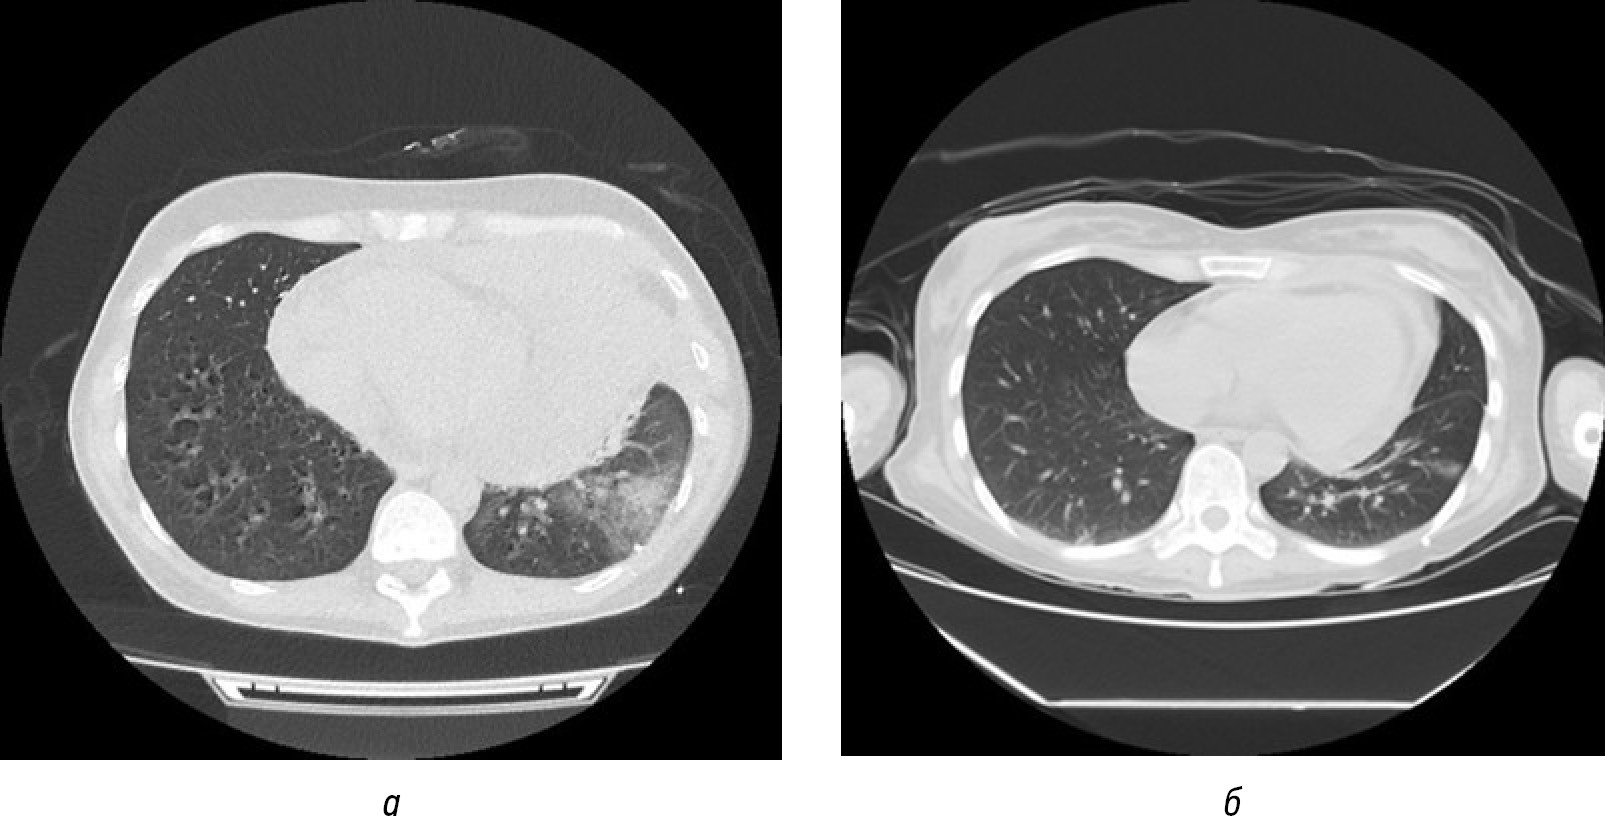

В связи с признаками дыхательной недостаточности пациентку госпитализировали в отделение реанимации и интенсивной терапии. Провели междисциплинарный консилиум, согласно заключению которого с учётом жизнеугрожающего состояния пациентки, обусловленного развитием тяжёлой дыхательной недостаточности с высоким риском летального исхода, было решено родоразрешить повторнобеременную в неотложном порядке с одномоментным проведением биопсии объёмного образования средостения посредством трансторакальной пункции для постановки гистологического диагноза и определения дальнейшей тактики ведения. Принимая во внимание тяжесть состояния пациентки, в качестве способа родоразрешения выбрали кесарево сечение. В связи с тяжёлой дыхательной недостаточностью чревосечение по Джоэлу–Кохену и кесарево сечение в нижнем маточном сегменте произвели в вынужденном положении пациентки на левом боку в условиях комбинированного эндотрахеального наркоза и эпидуральной анальгезии. В головном предлежании извлечён живой доношенный ребенок, росто-весовые показатели которого соответствовали физиологическим значениям для доношенного срока беременности. Оценка состояния новорождённого по шкале Апгар составила 7 и 8 баллов на 1-й и 5-й минутах жизни соответственно. Через 10 мин после извлечения ребёнка и последа у пациентки развилась брадикардия, однако в результате своевременно выполненных лечебных мероприятий нарушения сердечного ритма были устранены. Выполнены трахеобронхоскопия с выявлением компрессии объёмным образованием бифуркационной части трахеи и устьев обоих главных бронхов, а также эхокардиография с обнаружением признаков лёгочной гипертензии и гидроперикарда — произведена пункция перикарда и эвакуировано 240 мл серозно-геморрагического отделяемого. По результатам гистологического исследования материала, полученного посредством интраоперационной трансторакальной пункции объёмного образования средостения, морфологическая картина соответствовала лимфопролиферативному заболеванию — диффузной крупноклеточной В-клеточной лимфоме. В послеоперационном периоде состояние пациентки расценено как крайне тяжёлое, обусловленное прогрессированием признаков дыхательной недостаточности с развитием и нарастанием сердечной недостаточности, требовавшей комплексной многокомпонентной терапии, включавшей в том числе и заместительную почечную терапию для коррекции тканевой гипоперфузии. В условиях продолжавшейся искусственной вентиляции лёгких начали патогенетическую терапию преднизолоном с применением механической поддержки кровообращения в виде веноартериальной экстракорпоральной мембранной оксигенации. После стабилизации состояния родильница была переведена в стационар, профильный по оказанию специализированной медицинской помощи в рамках лечения лимфопролиферативного заболевания, где в условиях отделения реанимации и интенсивной терапии был начат курс комбинированной иммунохимиотерапии (ХТ+R) по схеме RCHOP. Через неделю наметилась стойкая положительная динамика в аспекте выраженного уменьшения размеров объёмного образования (рис. 2), активизации пациентки, возобновления самостоятельного питания и самообслуживания. Позже родильница была переведена в отделение гематологии с последующей выпиской из стационара и рекомендациями по дальнейшему наблюдению и лечению основного заболевания.

Рис. 2. Компьютерная томограмма органов грудной клетки с визуализацией объёмного образования средостения в лёгочном режиме, аксиальный срез: а — до иммунохимиотерапии; б — после первого курса иммунохимиотерапии.